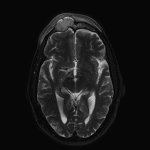

- Expansile lesion in the right frontal sinus with peripheral enhancement and central restricted diffusion measuring 3.5 x 2 x 2.5 cm

- Overlying thin peripherally-enhancing subgaleal collection along the superior margin of the frontal lesion with associated restricted diffusion and T2 signal hyperintensity and enhancement in the right frontal scalp

- Mass effect on the subjacent right frontal lobe with associated dural thickening and enhancement

- No discrete extraaxial collection or brain parenchymal signal abnormality

Expansile lesion in the right frontal sinus with peripheral enhancement and central restricted diffusion measuring 3.5 x 2 x 2.5 cm. This appearance is concerning for a mucopyocele (infected mucocele). Associated mass effect on the subjacent right frontal lobe with associated dural thickening and enhancement but no discrete extraaxial collection or evidence of cerebritis.

Overlying thin subgaleal abscess (along the superior margin of the collection) and cellulitis.